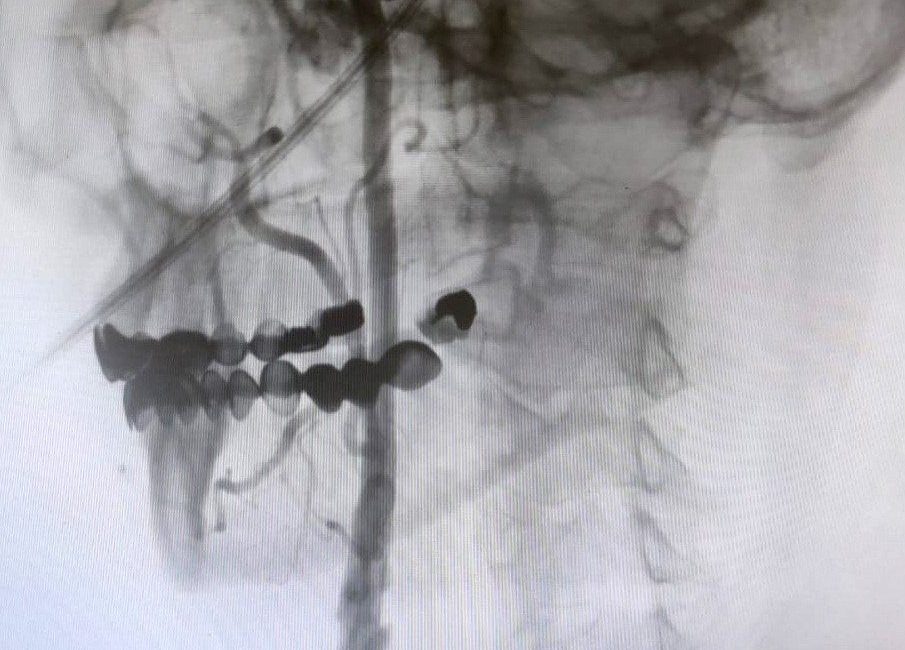

“Boyun damarlarını açma işlemi iki şekilde yapılabilir. Bir karotis endarterektomi dediğimiz ameliyatla bir diğer yöntem ise perkutan girişim dediğimiz stent yöntemiyle açılabilir. Biz kliniğimizde nöroloji ve kardiyoloji olarak bir konsey yapıyoruz. Damarı ciddi tıkalı olan ve buna bağlı felç geçirmiş hastalarda bu konseyde hastaya işlem yapıp yapmama kararı veriyoruz. Verdiğimiz karar çerçevesinde eğer hastaya işlem kararı vermişsek femoral arter dediğimiz kasık arterinden bir şitle 6 ya da 7 F çapında bir şitle ince bir boruyla bu damara giriş yapıyoruz ve boyun damarlarına ulaşıyoruz. Özellikle teller, filtreler ve stentlerle bu damarları açıp hastanın tedavisini gerçekleştiriyoruz. İşlem ameliyatsız olduğu için hastamız ertesi gün rahat bir şekilde problem olmazsa işlemde taburcu olabiliyor bu işlemden sonra. Bu işlemin yapılması için özellikle anjiografinin olduğu girişimsel nöroloji uzmanının ve girişimsel kardiyoloji uzmanının olduğu ve bu konuda yeterli vaka tecrübesine ve deneyime sahip uzmanların olduğu merkezler gerekir. Bunu yapabilmek için belli bir vaka sayısına ulaşmak ve bu konuda tecrübeli olmak gerekiyor. Biz de Manisa Şehir Hastanesi’ndeki girişimsel kardiyoloji ve nöroloji uzmanları olarak bu işlemi kliniğimizde efektif bir şekilde gerçekleştiriyoruz.”